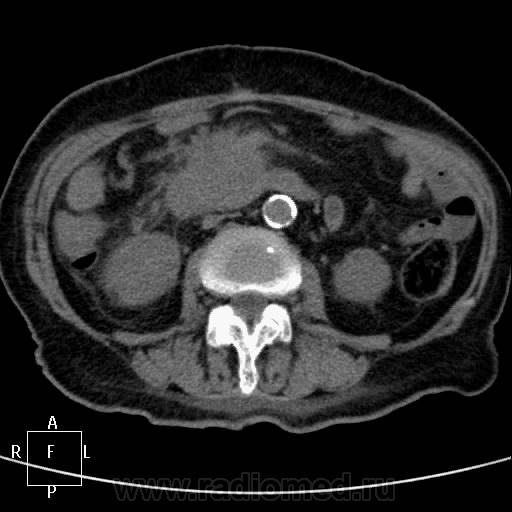

КТ поджелудочной железы. Пациентка 80 лет.

Упорные боли, кратковременно купируются ненаркотическими анальгетиками. Диастаза мочи 300. Кровь без особенностей. Псевдотуморозный панкреатит или опухоль? Опыта с панкреатитами - кот наплакал в знойный день))...

180 сек:

С левой почкой - кто такое видел? Атрофия средней трети и частично нижнего полюса, а в верхнем... помогите, пожалуйста!)) Вроде доброкачественное обызвествление. Не получилось напоить водой - несколько глотков и наотрез отказалась - тошнота. Поэтому 12-перстная безконтрастная практически.

На мой взгляд - опухоль головки ПЖ. Атроифя\ хоста и тела. Вирсунг расширен до зоны образования в головке - дальше четко не определяетя. Обычно при панкреатитах вирснуг хоть дефоримрованный но проходит через зону фиброзно-воспалиетльных изменений. Тут же похоже его обтурация.

На 45 секунде оразовние несколко гиподенсно по отношению к другой паренхиме (хотя и фиброз тоже такой будет).

Вообщим опухоль на мой взгляд головки ПЖ.

Согласен,кроме того,на 57-60 секундах в толще образования определяется ветвь верхней брызжеечной артерии.